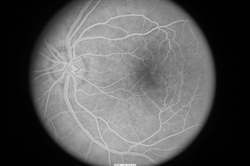

In addition, fluorescein angiography can be important to reveal abnormal and/or leaky vessels in the retina—this test requires an injection of a dye into the vein (usually in the arm or hand) before retinal photos are taken as the dye circulates through the blood vessels (Figure 4).